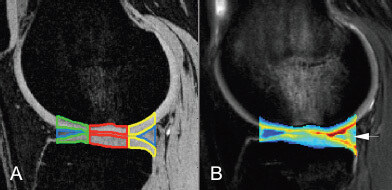

The Musculoskeletal Quantitative Imaging Research (MQIR) group consists of faculty members, postdoctoral fellows, research staff, and medical and graduate students who pursue their passion for teaching and research in quantitative tissue characterization focused on the musculoskeletal system.

Musculoskeletal Quantitative Imaging Research Directions